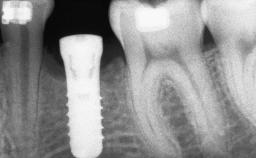

A 45-year-old woman with a completely edentulous maxilla was referred to evaluate the possibility of rehabilitation with an implant-supported prosthesis. This patient was healthy and a non-smoker. She had been wearing a maxillary complete denture opposing a natural mandibular dentition since her twenties. This situation had resulted in progressive resorption of the alveolar ridge, repeatedly creating a need for relining the denture. Twenty years later, despite multiple adaptations and the use of “glues” the denture was unstable and causing the patient psychological and functional discomfort.

Bone Augmentation Horizontal|Sinus Floor Elevation|Staged|Vertical

Augmentation Materials Autogenous chips|Autogenous block(s)

Bone Volume Deficient vertically or deficient vertically AND horizontally